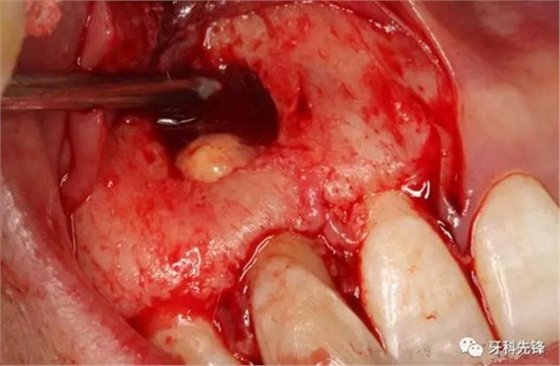

圖14.摘除后的囊腫情況,并用超聲骨刀清理根尖區(qū)后,可清晰看到12牙根未發(fā)育,根管粗大開放。

圖15.開放的根尖區(qū)用MTA封閉。